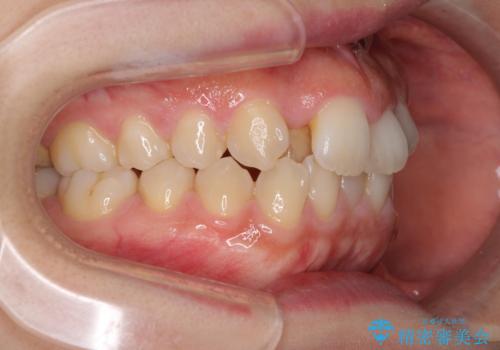

- 右上の八重歯と、左下八重歯を抜いてしまったことを気にして来院された患者様です。

下顎は既に犬歯を1本抜歯しているため、上顎右側第一小臼歯を抜歯し、ワイヤー装置にて歯列を整えることとしました。

変則的な抜歯となるため、正中と人中がずれる可能性がありましたが、仕上がりは上下正中を揃えることができました。